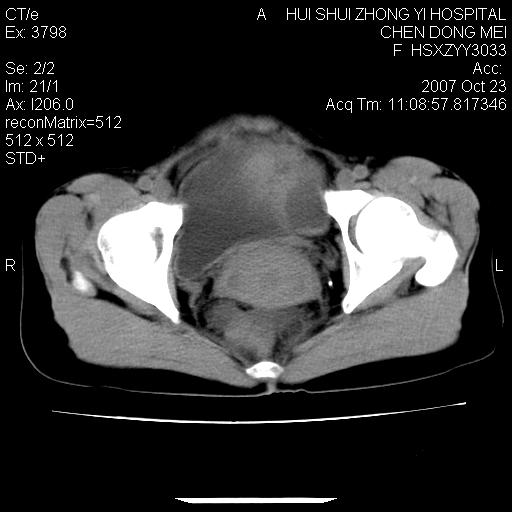

标题: CT10156:女.43岁,发现中下腹部包都块2年 [打印本页]

标题: CT10156:女.43岁,发现中下腹部包都块2年

发现中下腹部包都块2年。2年来月经不规律。

腹腔巨大软组织密度影,边缘光滑,包膜完整,内囊变坏死。腹膜后及盆腔内淋巴结肿大。结合病史考虑卵巢癌可能性大。

病变巨大,呈囊实性改变,包膜较厚且完整,内见分膈,周围脏器明显受压移位,病变与左侧附件关系密切,考虑来源左侧附件的囊腺瘤,不除外癌变可能;畸胎瘤可能性较小。

病变巨大,呈囊实性改变,包膜较厚且完整,内见分膈,周围脏器明显受压移位,病变与左侧附件关系密切,考虑来源左侧附件的囊腺瘤,盆腔内见肿大淋巴结,不除外癌变可能。